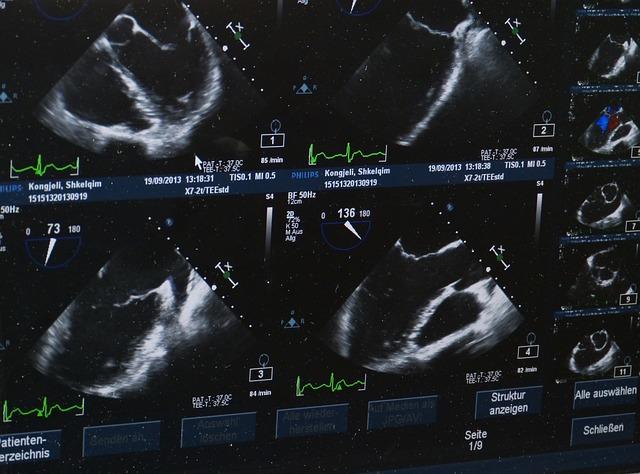

Ultrazvukové snímky během těhotenství jsou neocenitelným nástrojem pro monitorování vývoje plodu a zajištění zdraví matky. Gynekolog může pomocí ultrazvuku sledovat růst a pohyb plodu, stanovit termín porodu a odhalit případné komplikace či vady plodu.

- Transabdominální ultrazvuk - probíhá prostřednictvím senzoru umístěného na břiše matky.

- Transvaginální ultrazvuk - vyžaduje zavedení tenkého senzoru do pochvy pro lepší vizualizaci.

- 3D/4D ultrazvuk – poskytuje trojrozměrný obraz plodu a umožňuje sledovat jeho detailní tvary a pohyby.